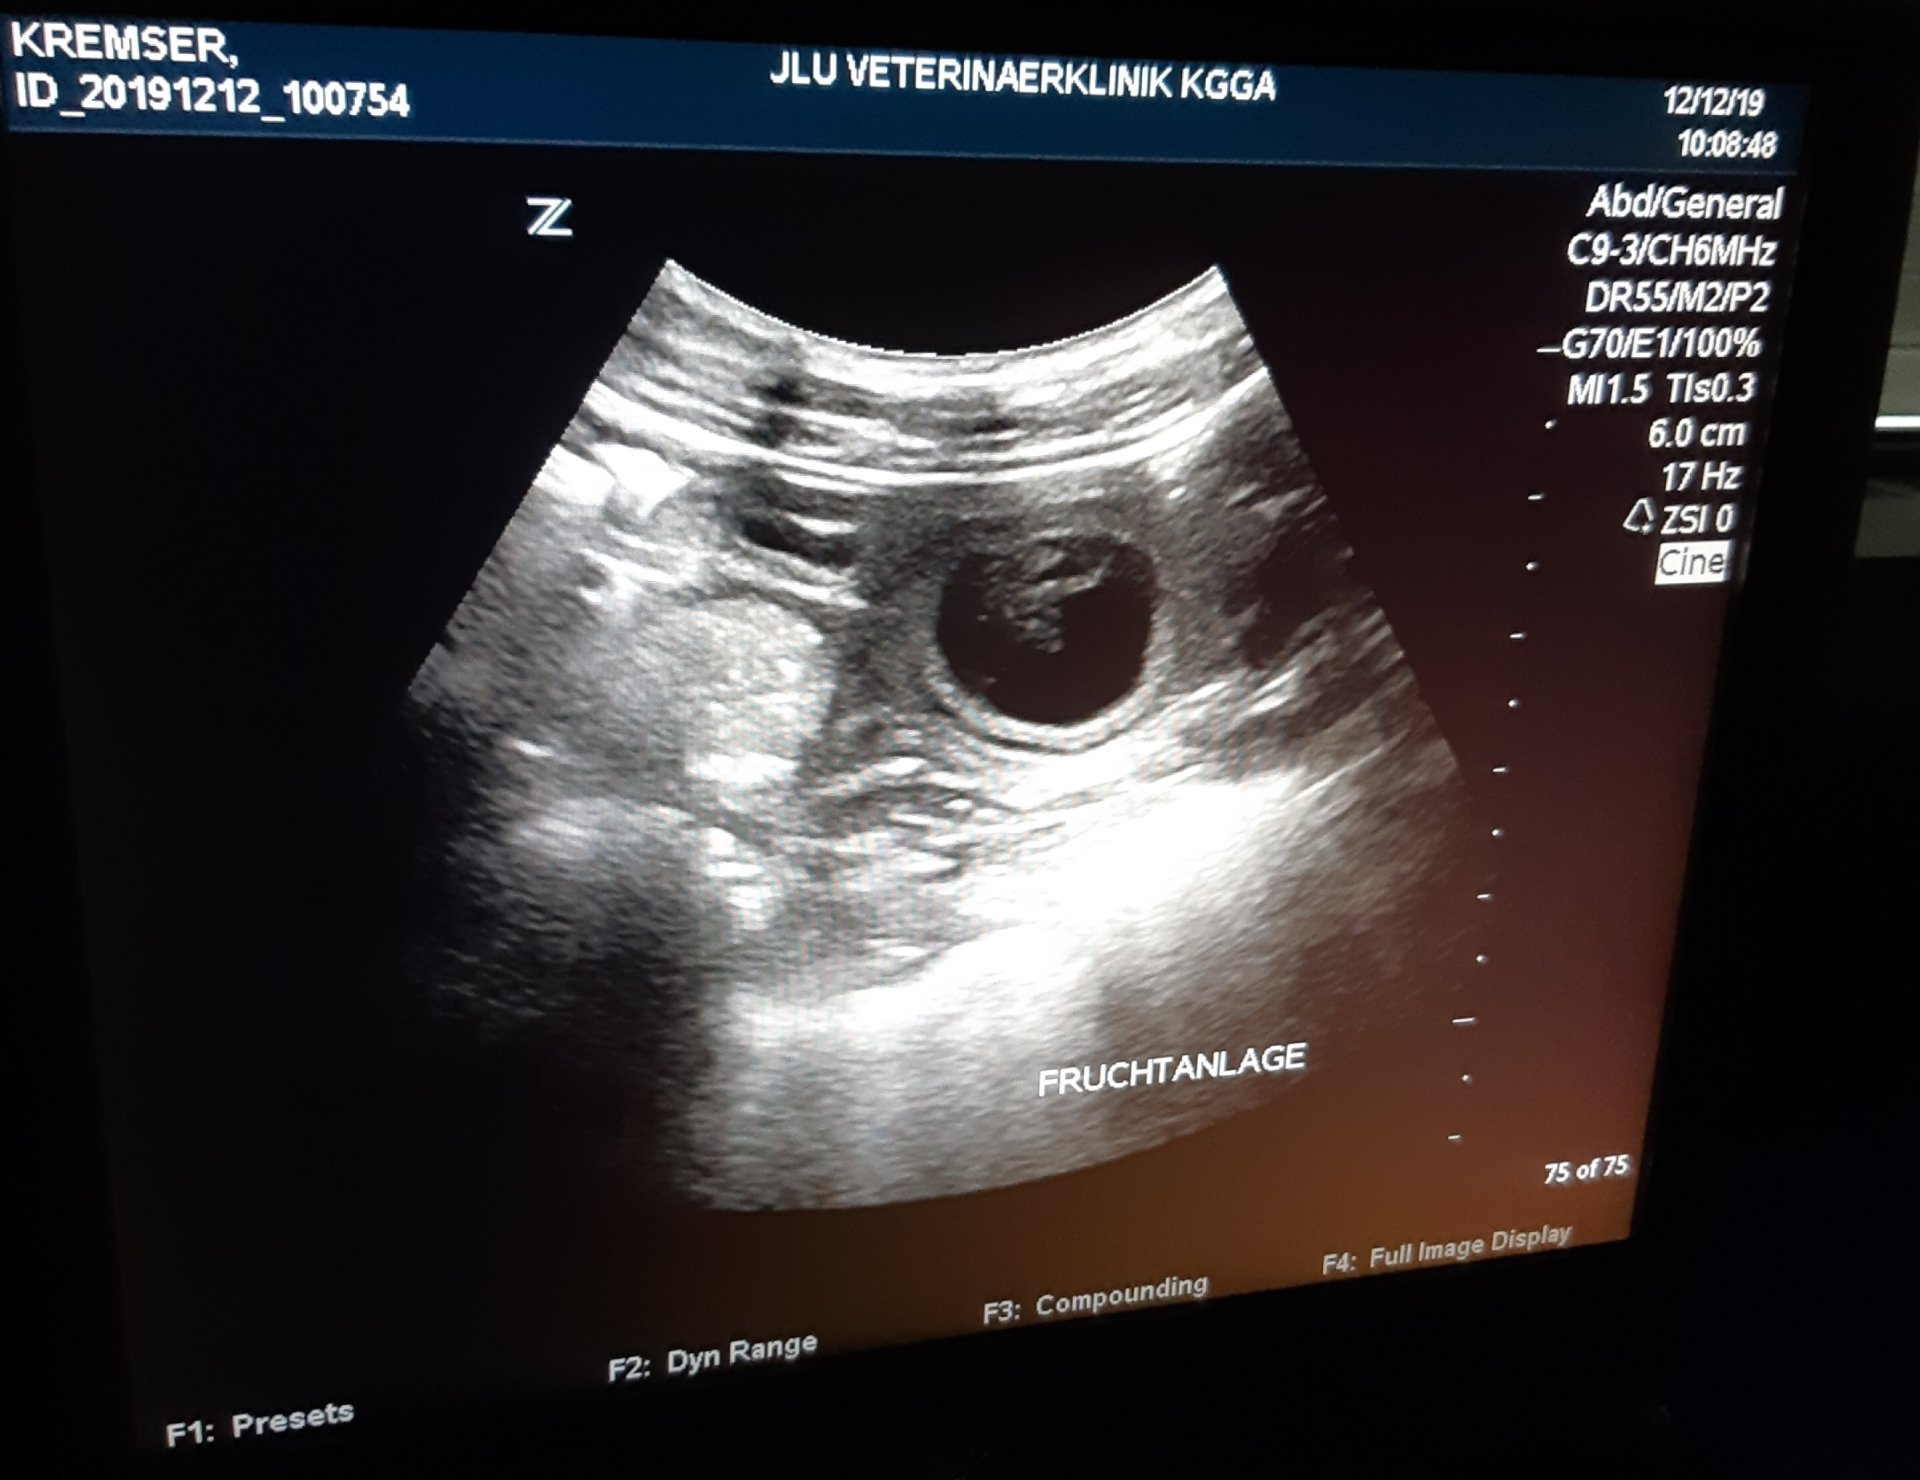

Die Strecken werden jetzt deutlich kürzer und langsamer und es werden vermehrt ruhige Spaziergänge gemacht, damit sie fit bleibt ohne sich zu überanstrengen. Spielaufforderungen und Herumhopsen im Garten gehen aber immer noch prima.